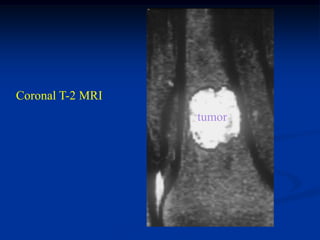

Case #555

55 year male

enchondroma

tibia

Bone scan

Coronal T-1 MRI

Coronal T-2 MRI

tumor